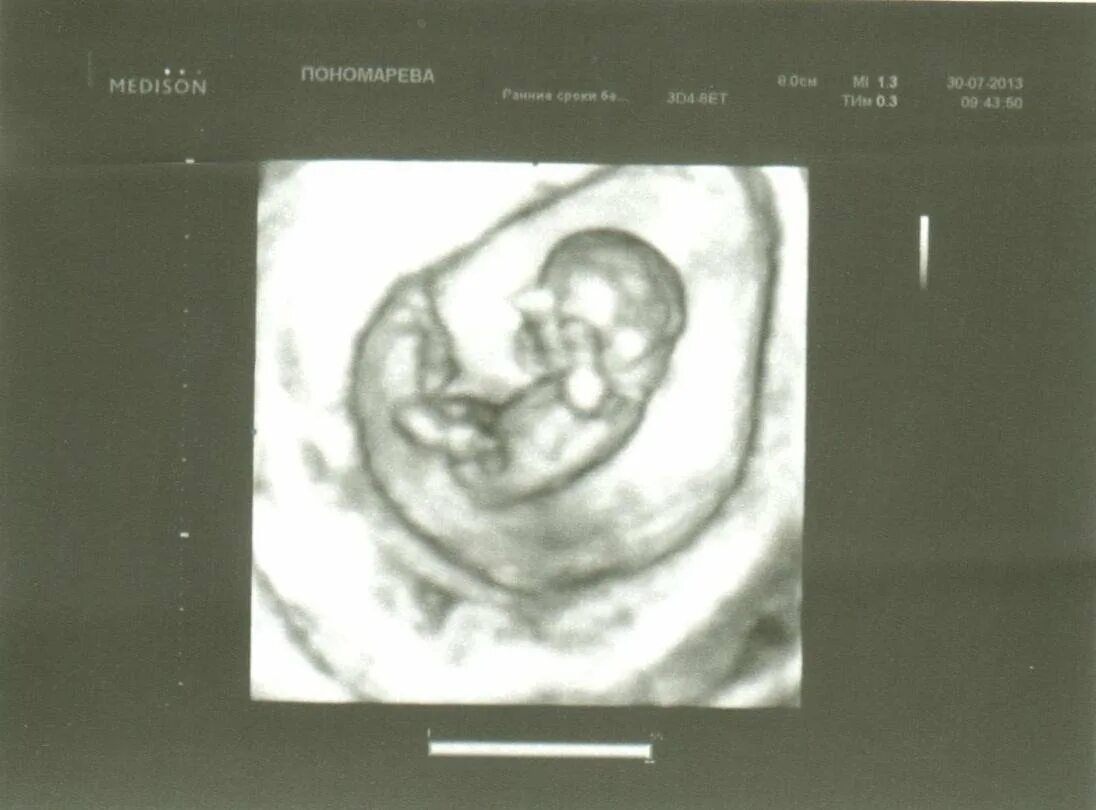

11 недель и 5 дней